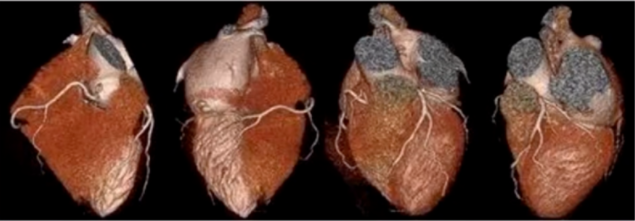

总的来讲,图像后处理有三种成像模式,分别是表面成像、曲面重建、冠脉探针模式。

1、表面成像

看冠脉的起源与分布,只能观察冠脉的起源、走行等大轮廓,不能看狭窄。

图13